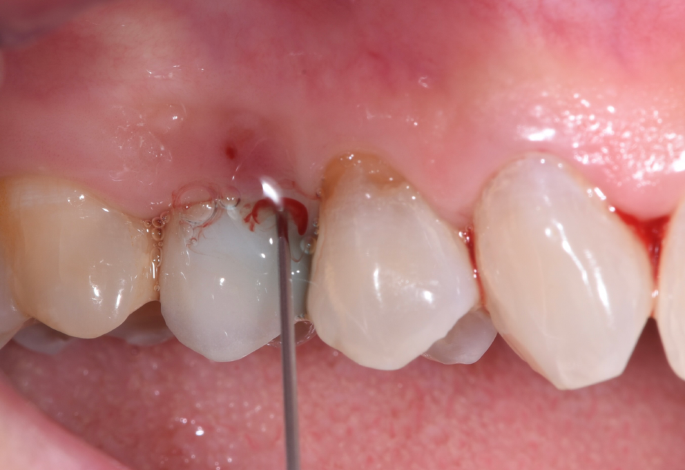

Diagnostic Methods

- Clinical Examination: Gentle probing (0.25N force) using plastic or metal probes to assess:

- Probing depths (comparing with baseline values)

- Bleeding on probing (BoP)

- Suppuration

- Mucosal recession

- Mobility (indicating complete loss of osseointegration in advanced cases)